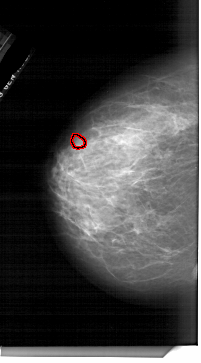

A_1761_1.LEFT_CC

LEFT_CC LINES 6526 PIXELS_PER_LINE 3601 BITS_PER_PIXEL 12 RESOLUTION 43.5 OVERLAY

FILE: A_1761_1.LEFT_CC.OVERLAY

TOTAL_ABNORMALITIES 1

ABNORMALITY 1

LESION_TYPE MASS SHAPE OVAL MARGINS ILL_DEFINED

ASSESSMENT 4

SUBTLETY 3

PATHOLOGY BENIGN

TOTAL_OUTLINES 1

BOUNDARY